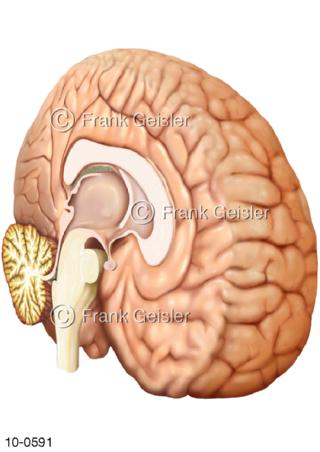

Bildergalerie Nervensystem

Bilder zum Nervensystem,dem Gehirn, Teil des zentralen Nervensystem, Zentralnervensystem ZNSmit Rückenmark, Abbildungen zum Nervengeflecht (Nervenplexus), die Verflechtungen von Nervenfasern, aus der Wirbelsäule hervortretende Nervenäst sowie Nervenzellen der Nerven